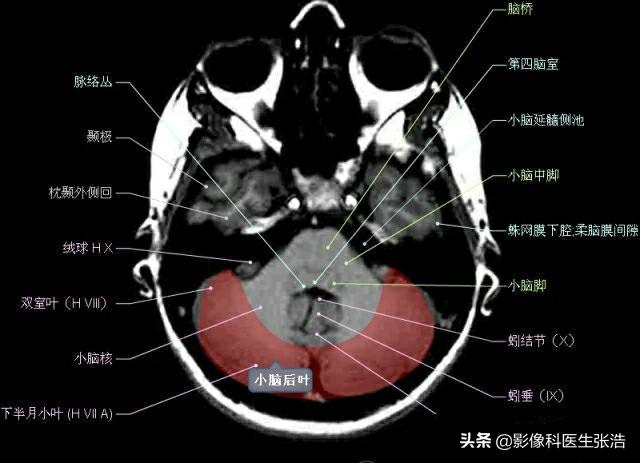

核磁共振(MRI)是一种利用磁场和射频脉冲来生成身体内部结构的详细图像的非侵入性检查技术,头部核磁共振主要用于检查脑部疾病、神经系统问题以及血管状况等,这项检查对于疾病的早期发现和治疗具有非常重要的意义。